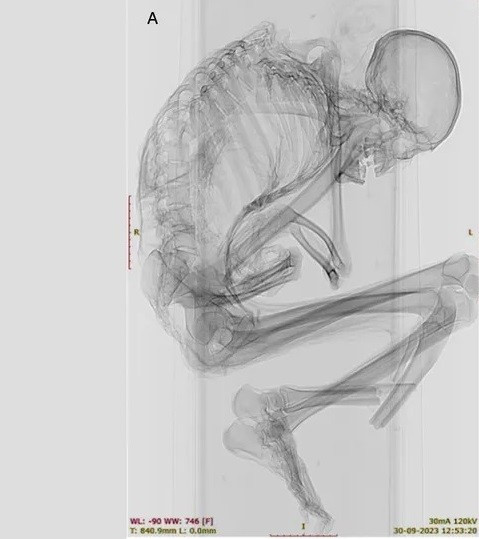

Kết quả kiểm tra xác ướp tìm thấy gần một mỏ ngọc lam ở sa mạc Atacama cho thấy người đàn ông này là một thợ mỏ tử vong trong vụ tai nạn lao động thương tâm.